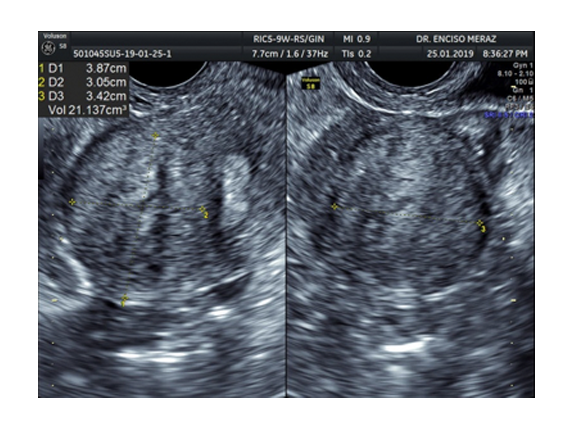

MIOMATOSIS

Leiomiomatosis, son los tumores benignos uterinos mas frecuentes de la mujer.

Se originan de las celulas musculares del utero. Tienen una frecuencia del 30% de todas las mujeres, estando con mayor frecuencia en la decada de los 30 y 40 años.